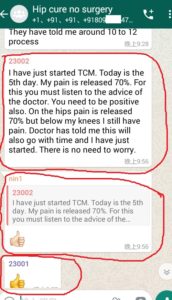

1. The Gentleman in Kenya started his treatment at his home April 27, now he said: (will update his more progresses soon)

3. The gentleman in India just started May, 2019. Actually he started on April 28, 2019 but he used it in wrong way and got less effects, ONLY on May 8, 2019 during our follow-up, we found his wrong-doing, and then corrected him. ONLY in 2 days, his pains significantly reduced!!!!